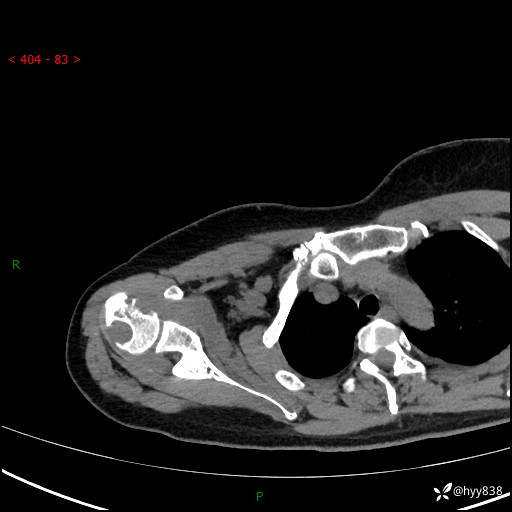

右肩关节CT平扫